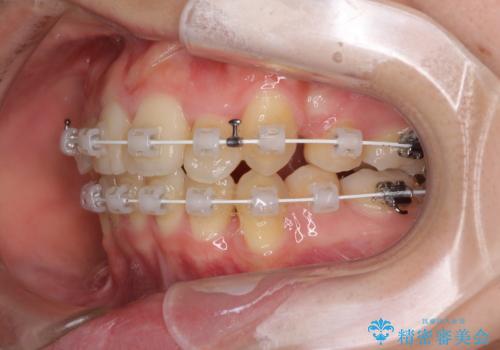

気になる八重歯を治したい ワイヤー装置での抜歯矯正

- 上下の八重歯や乱杭歯を気にして来院され患者様です。

スペースを確保するため、上下左右の第一小臼歯を抜歯し、ワイヤー装置に矯正することとしました。

結婚式の予定があったため、まずは前歯をきれいに整えるようにしました。

結婚式の時には一時的に前歯の装置を外し、口元を気にせず笑える結婚式を迎えることができました。

その後スペースを閉じるために時間を要しましたが、満足のいく仕上がりとなりました。